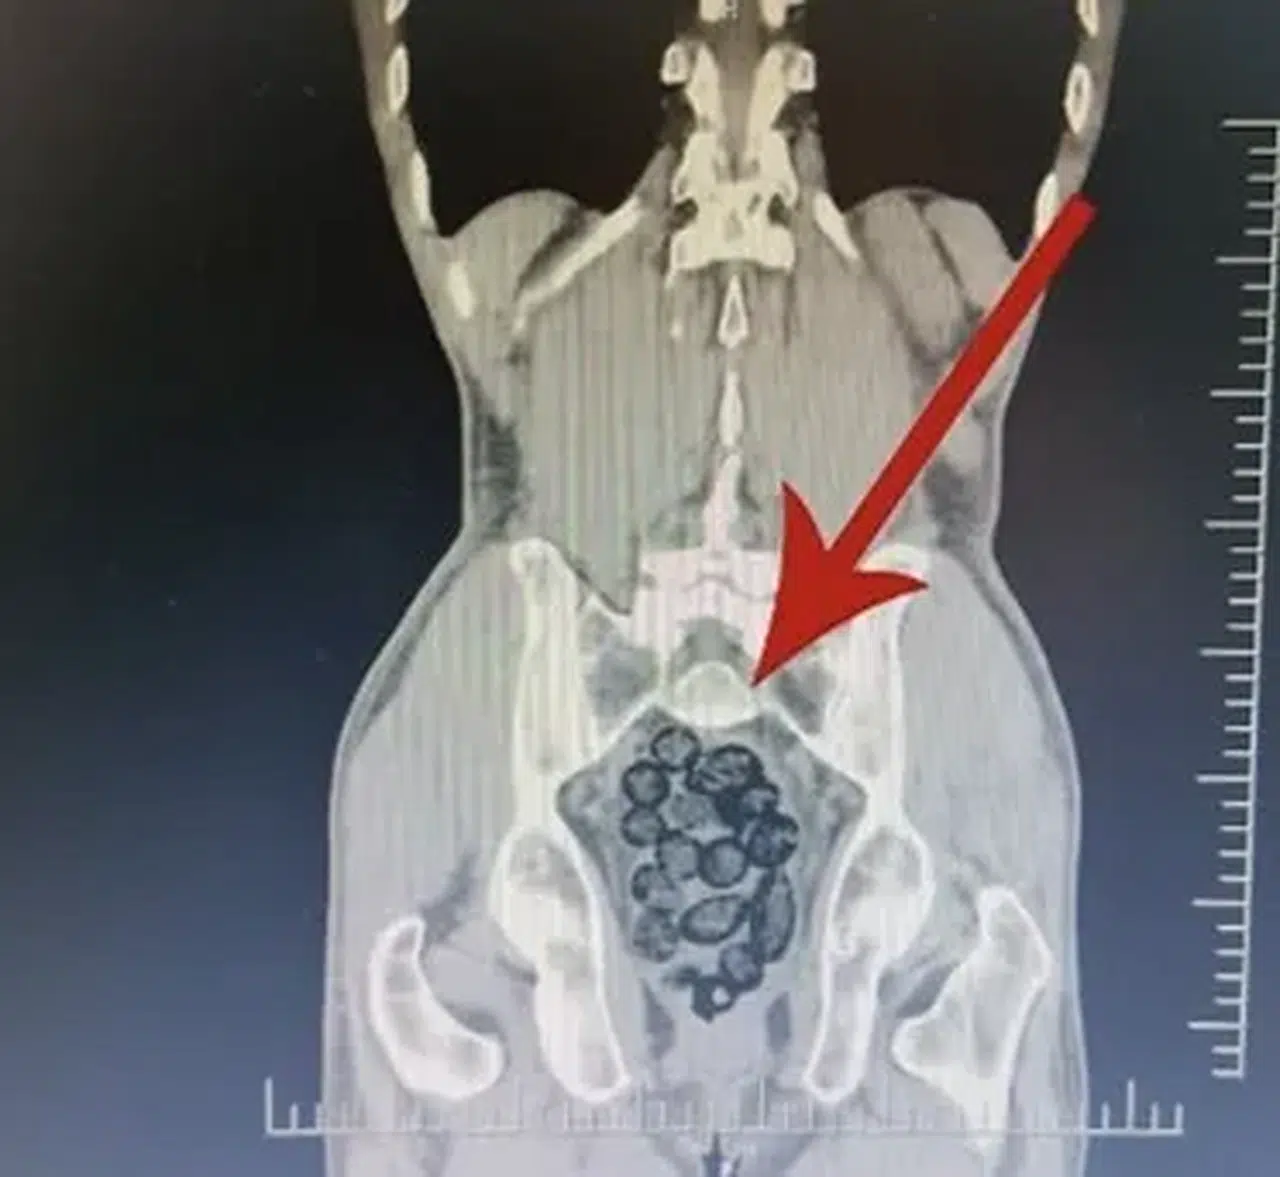

Batman’da durdurulan otobüste midesinden 64 parça metamfetamin çıkan yabancı uyruklu yolcu, polis operasyonuyla yakalanarak tutuklandı.

Batman’da durdurulan otobüsteki yabancı şahsın midesinden 64 parça uyuşturucu maddesi metamfetamin çıktı.

Batman İl Emniyet Müdürlüğü Narkotik Suçlarla Mücadele Şube Müdürlüğü ekiplerince Batman Cumhuriyet Başsavcılığı koordinesinde yürütülen çalışmalar kapsamında Batman girişinde durdurulan otobüste arama yapıldı.

Durumundan şüphelenilen yabancı uyruklu bir yolcu üzerinde arama yapıldı. Yapılan incelemeler sonucunda yabancı uyruklu şahsın midesinde 64 Parça halinde toplam 472 gram uyuşturucu maddesi metamfetamin olduğu belirlendi.

Gözaltına alınan şahsın midesindeki uyuşturucu madde çıkartıldı.